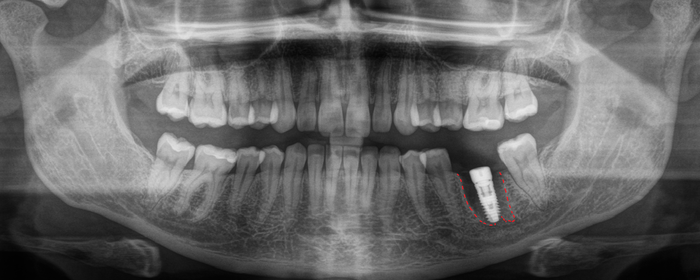

А теперь пример синус-лифтинга и имплантации, но через 2 месяца после того, как был удален 6-ой зуб на верхней челюсти. Этой пациентке удалили 6-ку около недели назад в другой клинике. Ассистентка сделала компьютерную томографию.

В связи с тем, что после удаления прошла всего неделя, то и на снимке мы видим «темную дыру», как ту, что оставила в твоем сердце бывшая. В том месте, где раньше был зуб. То есть костной ткани в этой области нет. К операции я приступил через 2 месяца. Повторную компьютерную томографию после заживления лунки делать не стали, но поверьте все зажило достаточно для того, чтобы можно было провести операцию. В ходе операции жесткой стабилизации имплантата добиться не удалось, поэтому я принял решение установить заглушку, а не формирователь десны. Почему? А потому, что если пациентка начнет грызть сухари, то на имплантат, в частности формирователь, может быть оказано сильное давление, в связи с чем имплантат может расшататься или «улететь» в пазуху. Заодно в утиль пошла и 8-ка.

Ну и последний пример на сегодня — удаление 2-х зубов, установка 2-х имплантатов и синус-лифтинг.

Как мы видим условия в данном случае несколько хуже около 2мм. Но это не помешало нам провести операцию в полном объеме.